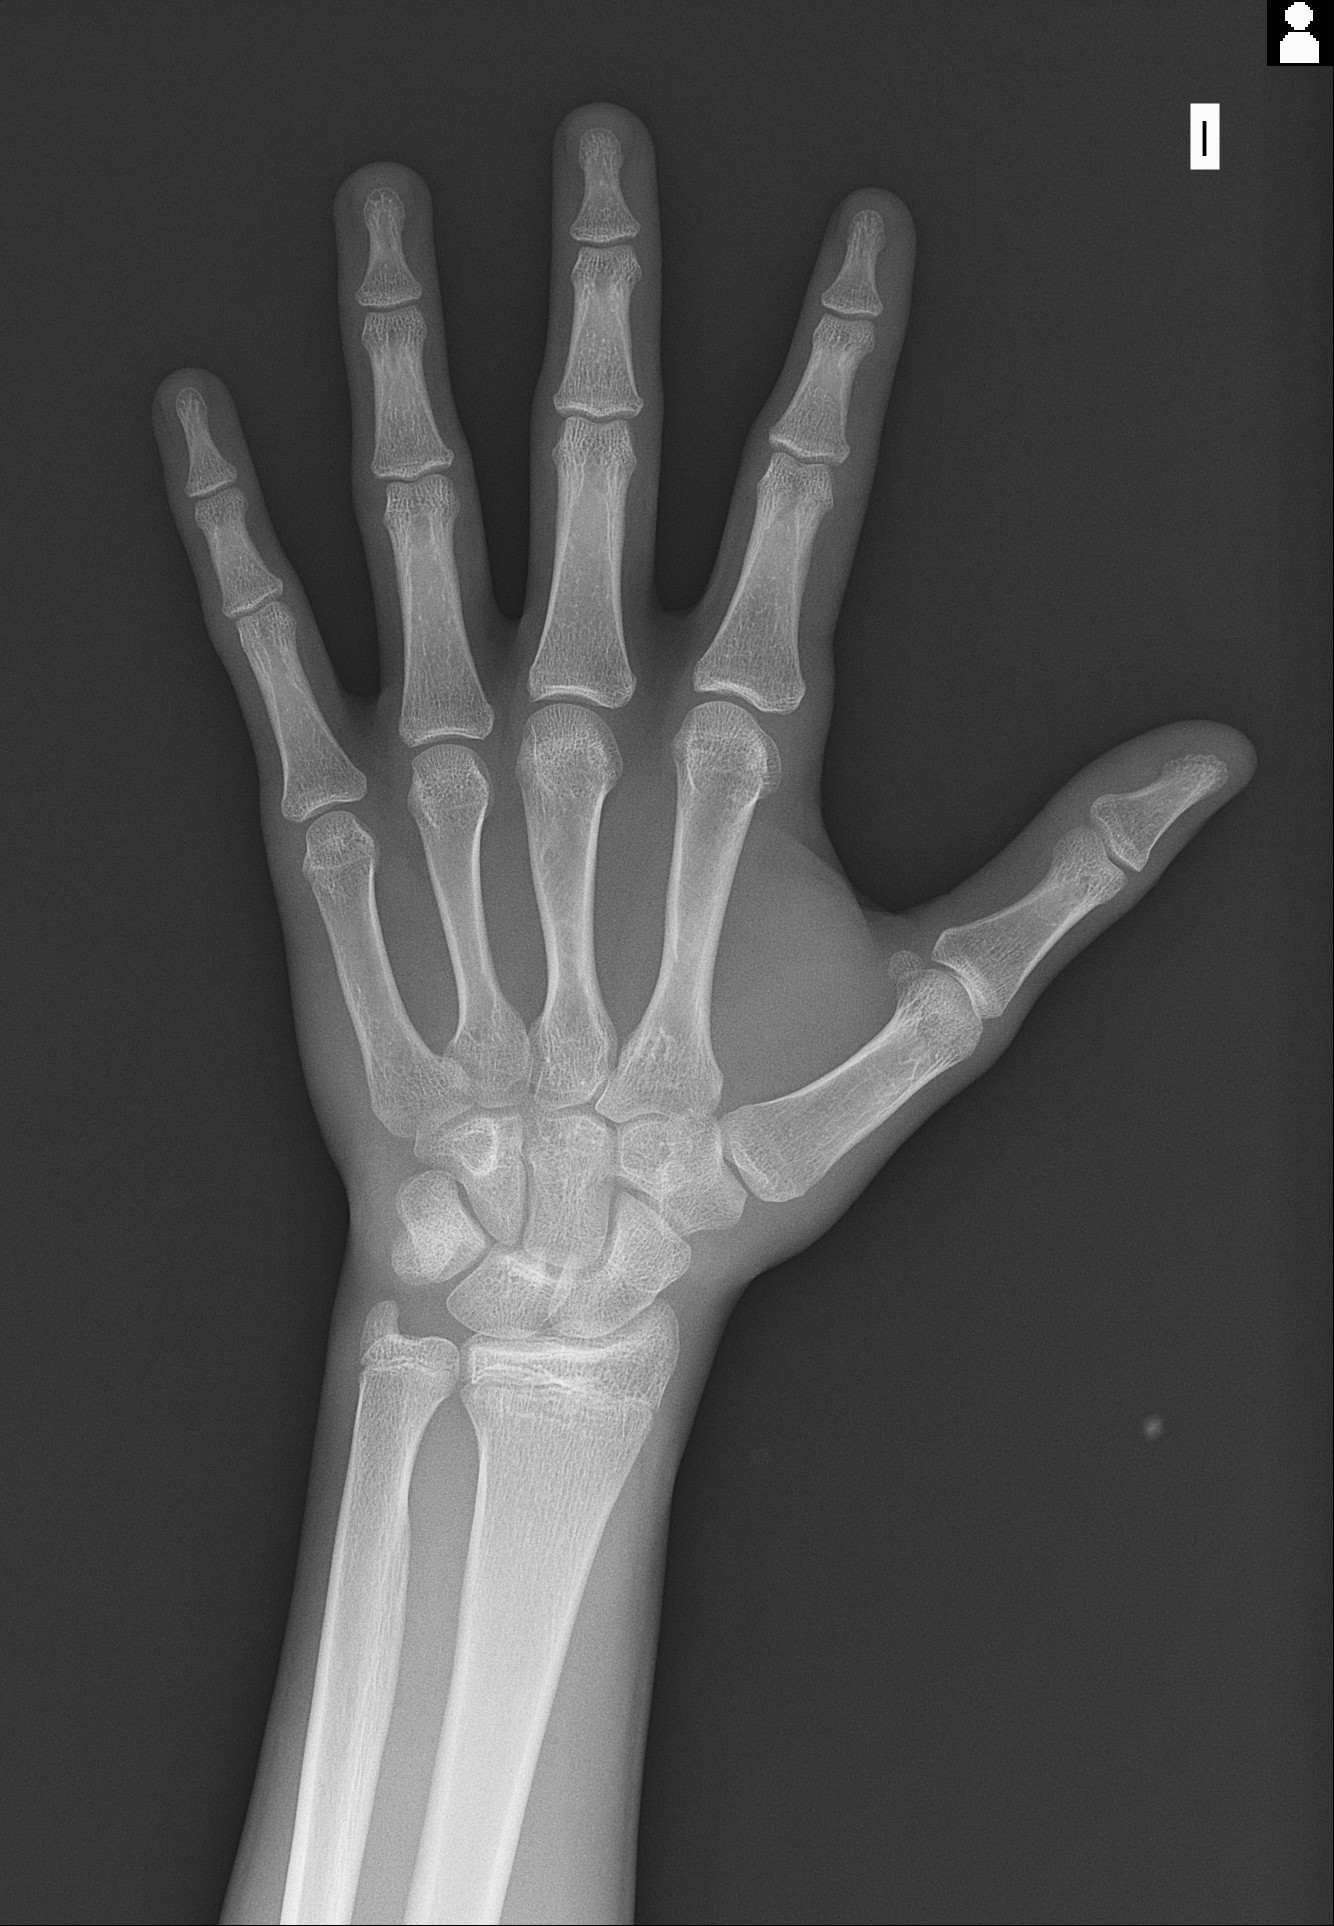

22.01.2026 x-ray of growth plates

Is it worth it to take them to get more time to grow?? My age is 16 and 17 in less than 3 months. My bone age is 5 months older than me based on my calculations (used orkas thread on radiology https://looksmax.org/threads/the-ra...s-how-to-tell-if-youre-still-growing.1701312/). Would I gain more than 3cm extra with ai? Regarding also the risk of osteoporosis or bad brain development.